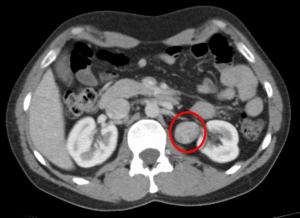

My unexpected diagnosis

PVNS – One year On Post Surgery

Tumor